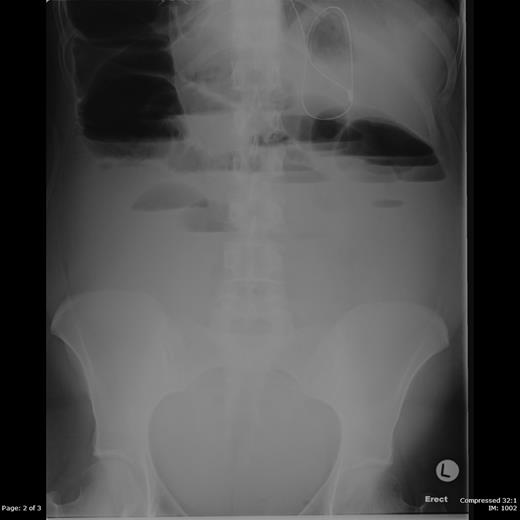

Increasing analgesic and antiemetic requirements prompted induction of labour at 38 weeks and 4 days gestation, with vaginal delivery of a baby boy. Despite clinical improvement initially, symptoms worsened again 24 h postpartum. She was no longer passing flatus and there were no audible bowel sounds. Repeat abdominal radiograph showed a large bowel obstruction with caecal dilatation up to 13 cm (Figures 1 and 2). The small bowel was also dilated, up to 5 cm.

Supine abdominal radiograph showing dilated loops of both large and small bowel.